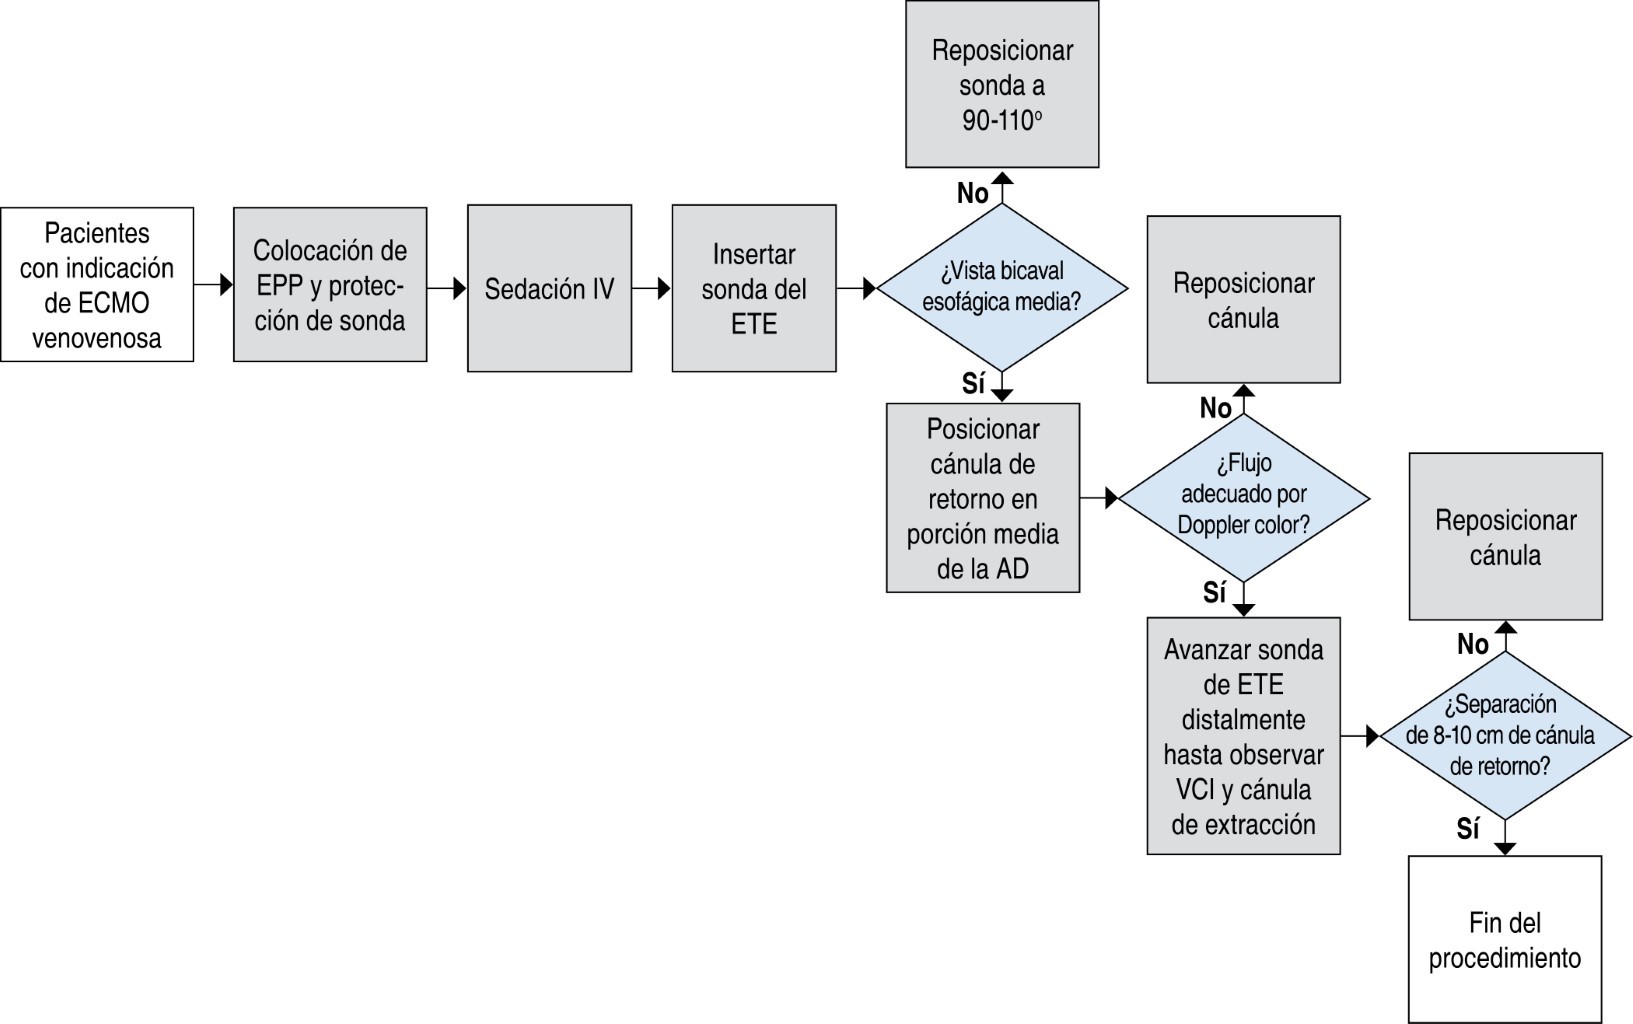

Como primer paso del flujograma (Figura 1), todo el personal debe tener una EPP adecuada y proteger la sonda del ETE (Figura 2A). Después de la sedación intravenosa, se inserta la sonda de ETE, siendo la proyección seleccionada para guiar el procedimiento la vista bicaval esofágica media de 90-110 grados (Figura 2B), donde podemos guiar en tiempo real el posicionamiento correcto de la cánula de retorno (yugular) (Figura 3A), que debe colocarse en la porción media de la aurícula derecha en dirección a la válvula tricúspide. El flujo adecuado puede evaluarse mediante Doppler color (Figura 3B). La sonda de ETE con el mismo grado de angulación se avanza distalmente hacia el esófago para observar la vena cava inferior y la cánula de extracción (femoral) que debe estar separada 8 a 10 cm de la cánula de retorno (Figura 3C y D); esto limita los fenómenos de succión y recirculación.